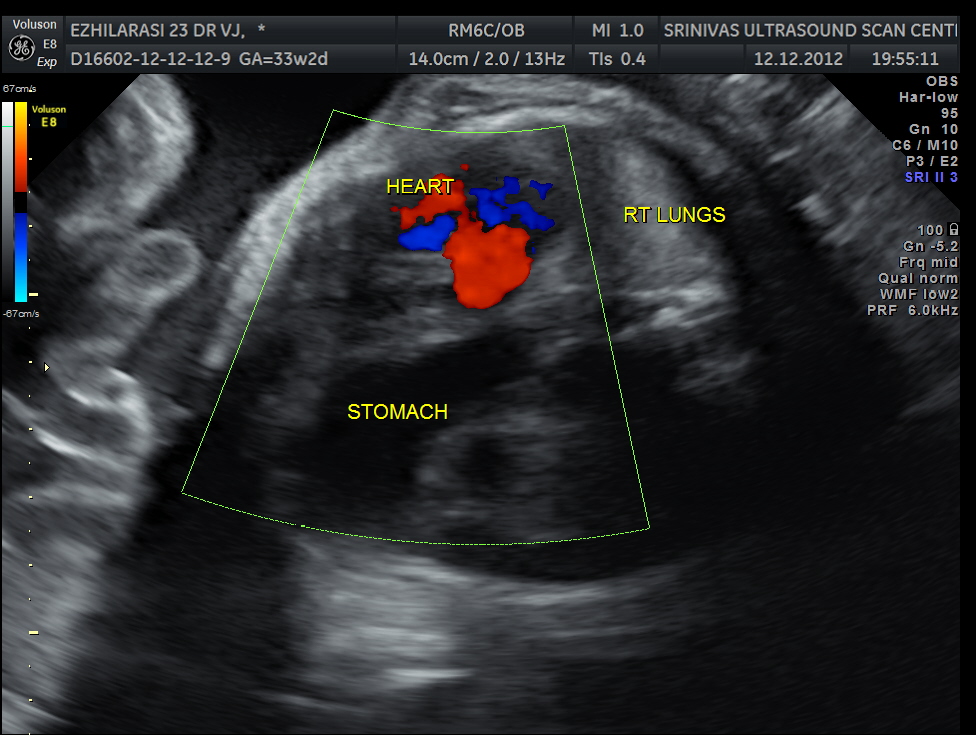

The heart was seen in the right side of thorax . The left hemithorax showed the stomach bubble and bowel loops suggestive of Congenital Diaphragmatic Hernia .